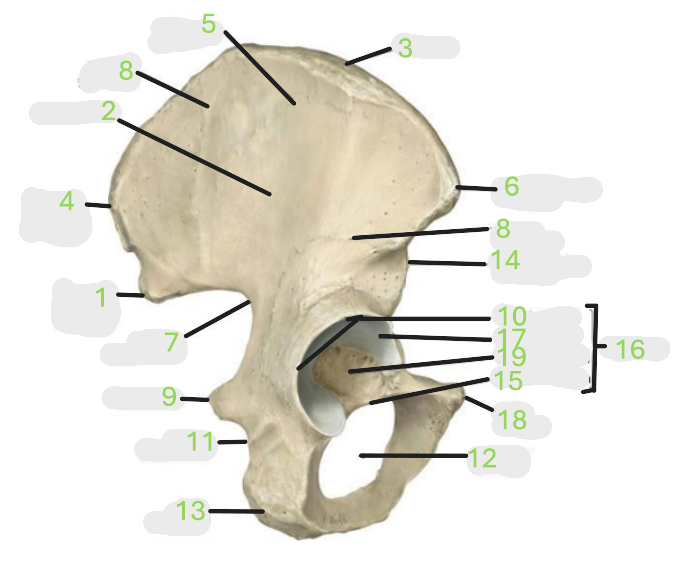

Where is the posterior inferior iliac spine

1

Where is the gluteal surface

2

Where is the iliac crest

3

Where is the posterior superior iliac spine

4

Where is the anterior gluteal line

5

Where is the anterior superior iliac spine

6

Where is the greater sciatic notch

7

Where is the inferior gluteal line

8

Where is the ischial spine

9

Where is the acetabular rim

10

Where is the lesser sciatic notch

11

Where is the obturator foramen

12

Where is the ischial tuberosity

13

Where is the anterior inferior iliac spine

14

Where is the acetabular notch

15

Where is the acetabulum

16

Where is the lunate surface

17

Where is the pubic tubercle

18

Where is the acetabular fossa

19